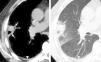

En los casos en que hubo dudas sobre la cobertura adecuada del tumor por los electrodos o para delimitar adecuadamente la relación con las estructuras vecinas, se realizaron reconstrucciones multiplanares y/o proyecciones de máxima intensidad (fig. 1). Para las lesiones de más de 3cm, ante la duda de que hubiera una cobertura adecuada del tumor, se hicieron esferas solapadas.

ResultadosProcedimientoEn todos los pacientes en que se programó el tratamiento con RF el procedimiento se llevó a cabo con éxito. En los pacientes tratados con finalidad curativa se definió como éxito técnico la cobertura completa del tumor, con el desarrollo de un halo de patrón alveolar alrededor como margen de seguridad (fig. 2). En los casos tratados con finalidad paliativa se consideró éxito técnico la ablación completa de la pleura parietal en contacto con la neoplasia.

Cuando toda la lesión ha sido adecuadamente tratada, en el control inmediatamente posterior al tratamiento aparece un halo en vidrio deslustrado (flechas huecas). Nótese la oquedad lineal en el trayecto de inserción de la aguja (flecha). Hemorragia parenquimatosa visible en la tomografía computarizada realizada inmediatamente después de la ablación mediante radiofrecuencia.